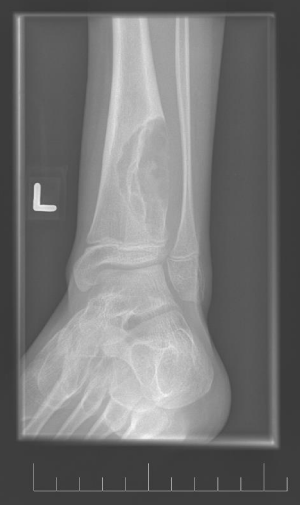

A 10-year-old female presented with left lower leg pain that had progressively increased over the duration of 1 year. On physical examination, tenderness was elicited on palpation of the distal tibia. Routine laboratory testing was normal. X-Ray was performed and revealed a lytic lesion with sclerotic margins in the left lower tibia (Figure 1). MRI was subsequently performed, demonstrating a left lower tibia lesion with low signal intensity on T1 weighted images (Figure 2), and high signal intensity on T2 weighted images (Figure 3). Pathology of the tumor revealed a diagnosis of a CMF. She was treated with curettage and autologous bone grafting (Figure 4). Post op eratively the left leg was immobilized with a plaster cast with restricted weight bearing (Figure 5). Follow up X-ray after 5 years demonstrates no tumor reoccurrence (Figure 6, Figure 7).

Figure 1: Initial lateral X-ray of the left ankle.